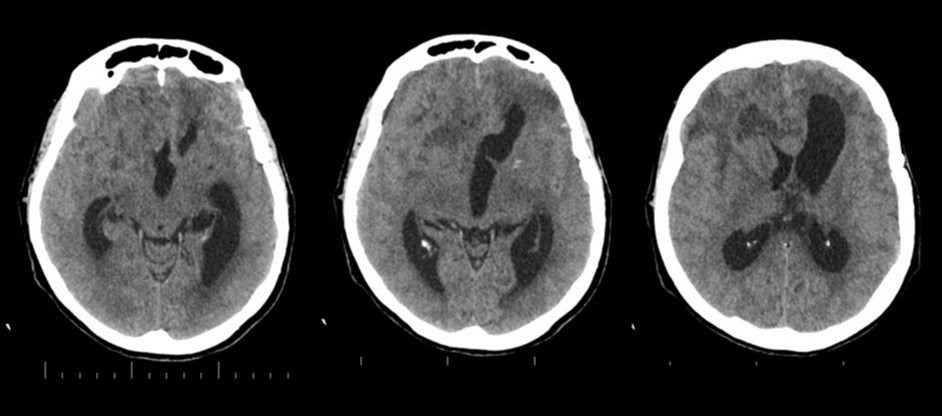

The follow-up CT scan made two weeks later showed a mild ventricular enlargement and persistent density alterations in the frontal region (Figure 2) that were interpreted as normal. Once discharged at home, the patient developed progressive disorientation that finally let her refer to our hospital for consult four months after aneurysm clipping. The cerebral CT we performed showed further ventricular growth, and a tumor-like image in the right frontal lobe (Figure 3). She was admitted to our ward and underwent a contrast-MRI that confirmed the suspicion of aggressive intra-axial neoplasm (Figure 4). The week after, under general anesthesia we performed a right craniotomy and removed a large part of the tumor, sparing the portion going through the corpus callosum (Figure 5). During convalescence the patient had few epileptic attacks, treated with drugs. A mild cognitive impairment persisted after surgery, without focal motor deficits. The gait, limited and unstable since the SAH, remained poor and the patient never walked again after the operation. The histological examination indicated a WHO grade IV glioma: IDH1-p53 negative glioblastoma. The patient and her relatives refused a ventriculo-peritoneal shunt after knowing this unfortunate diagnosis. Transferred to rehabilitation, the woman made just a short low-dose chemotherapy cycle and finally died four months after tumor resection.

Figure 3.4 months non-contrast CT scan. Ventricles are dilated. A mass clearly affects the right frontal and midline region

The clinical and radiological features of these two diseases are perfectly known to neurosurgeons; anyhow our case shows that trouble rises when they do occur simultaneously. The patient we described had initially acute signs due to SAH and later signs that were incorrectly interpreted as SAH-related. The tumor was almost invisible -because of its likely small volume and thick SAH- in the first CT performed (Figure 1). Analyzing the early follow-up CT (Figure 2) anyway things do not seem so clear. In the frontal region remained too much fogging close to the midline; the asymmetric distribution of such alteration should had point out a problem, but everybody kept thinking to a “simple” post-hemorrhagic condition, due to ventricular enlargement and focal ischemia. The initial mental impairment of that period was equally attributed to a normal SAH result with moderate hydrocephalus. The proper diagnosis of glioma happened late, and the patient was at that point unable to have significant benefits from surgery.